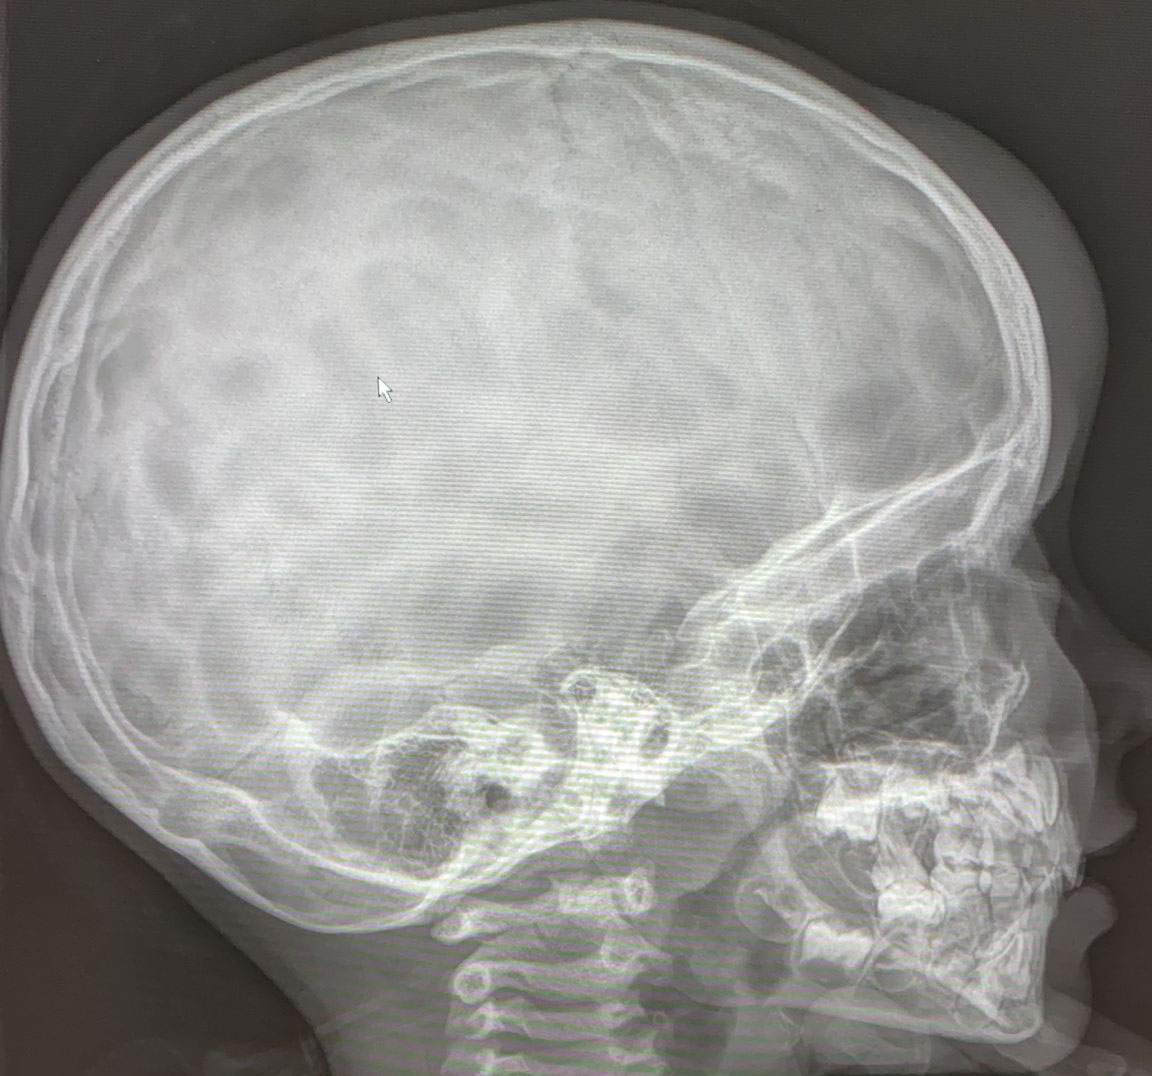

SIGNO DEL ALGODÓN

El signo del algodón hace referencia al aspecto que tiene el hueso en la radiografía de cráneo en pacientes con enfermedad de Paget. Se observa un engrosamiento de la calota en la que existen focos de esclerosis parcheados y de aspecto borroso que resaltan sobre un hueso de menor densidad.

En la literatura angloamericana también se ha descrito el Signo de Tam O´shanter para describir la afectación por enfermedad de Paget de la calota. El Tam O´shanter es la boina escocesa, que recibe el nombre del personaje de un poema narrativo de Robert Burns publicado en 1791. Con este nombre se describe el aspecto del cráneo en la proyección lateral, como envuelto por una boina o gorro.